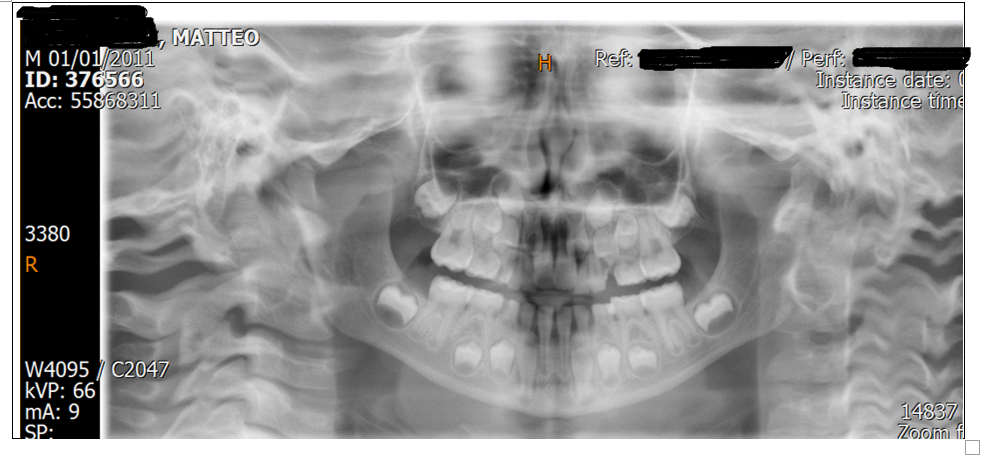

Ultimi casi clinici

Una selezione dei trattamenti completati di recente